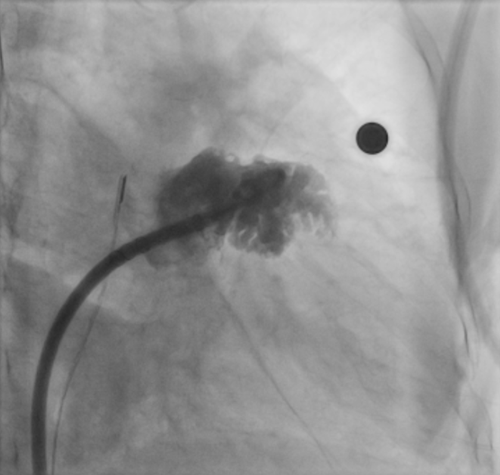

术后三维心腔内超声复查左心耳稳定性

经过术前准备,手术顺利开展,整个手术过程不到2小时,三维心腔内超声在术前对左心耳大小进行测量,术中指导房间隔穿刺,术后评估封堵位置及稳定性,术后李奶奶自述没有任何痛苦,在手术台上睡了一觉就解决了房颤对她带来的困惑,术后恢复已出院。

4、提高手术精准度。术中可通过三维重建,全面了解左心耳及其辅助结构的解剖关系。

5、提高安全性。通过三维心腔内超声实时监测心脏解剖结构,既是手术成功检测的金标准,又是手术安全的必要保障,能第一时间发现潜在并发症,降低手术风险。